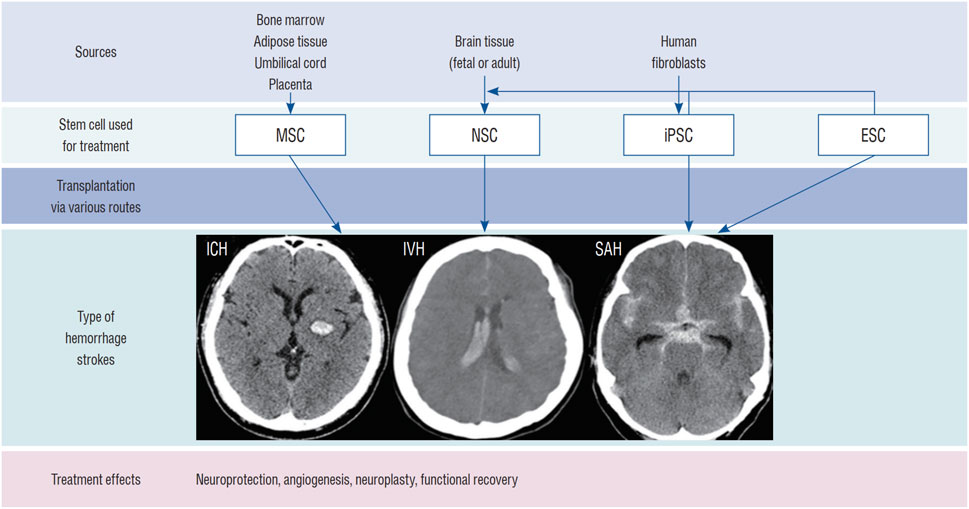

推进脑出血的干细胞治疗需要整合生物材料、基因工程和预处理策略以提升疗效。尽管前景看好,但目前仍缺乏大规模、设计严谨的脑出血临床试验和长期安全数据(图3)。未来研究需着重优化给药途径、剂量、时机以及符合药品生产质量管理规范的大规模细胞制备工艺。

图3:用于治疗ICH的干细胞类型:该图显示了用于治疗ICH(脑实质出血、脑室内出血[IVH]和蛛网膜下腔出血[SAH])的干细胞类型,包括 NSC、间充质干细胞 (MSC)、诱导多能干细胞 (iPSC) 和胚胎干细胞 (ESC)。